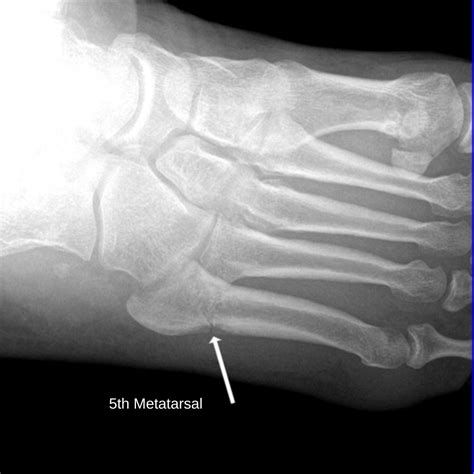

When you feel a hard, protruding bone on outside of foot, it is frequently the fifth metatarsal head. This is the large bone that connects to your pinky toe. In a healthy foot, this bone sits relatively flush with the rest of the foot’s structure. However, several factors can cause this area to become more pronounced, painful, or inflamed.

While home remedies are often sufficient for mild cases, persistent or worsening pain necessitates a visit to a specialist. A podiatrist can perform physical exams and utilize imaging, such as X-rays, to see if the bone on outside of foot is the result of a skeletal alignment issue or a soft tissue condition.